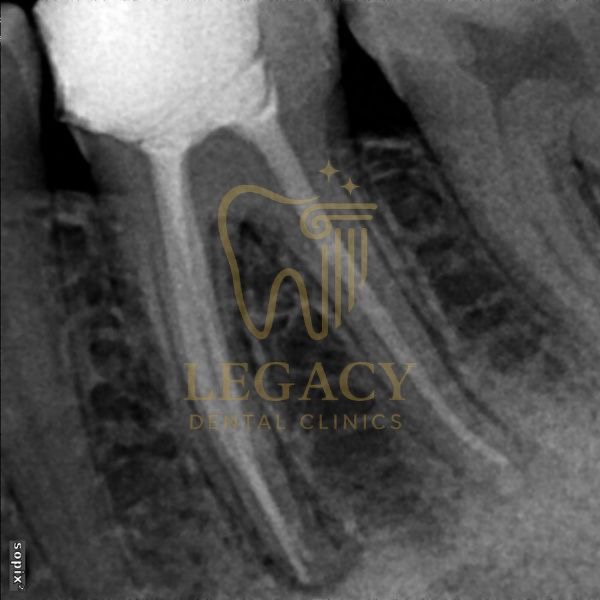

حالة زراعة فورية لسن أمامي - د.عمر نافوخ